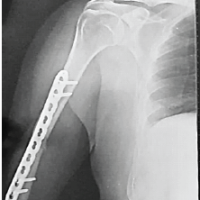

Surgical technique

All surgeries were performed under spinal anesthesia on a fracture table, with the affected limb placed in traction and adduction to facilitate anatomical reduction under C-arm fluoroscopic guidance. A standard lateral incision centered over the greater trochanter was used for surgical exposure. Closed reduction was attempted in all cases, whereas open reduction was reserved for irreducible fractures. The entry point for nail insertion was made at the tip or slightly medial to the greater trochanter using an awl. A PFN of appropriate diameter (ranging from 9 to 12 mm) and length was inserted over a guidewire, with the neck-shaft angle varying between 125° and 135°, selected according to patient anatomy and fracture pattern. Proximal locking was performed using two screws – a lag screw and a derotation screw – under fluoroscopic control, ensuring that the Tip-Apex Distance (TAD) was maintained below 25 mm to minimize the risk of screw cut-out. Distal locking was carried out either dynamically or statically, depending on the stability of the fracture configuration. Finally, a layered closure was performed after confirming satisfactory reduction, nail placement, and screw positioning under fluoroscopy. Intraoperative parameters such as operative time, blood loss, and any technical complications were recorded.